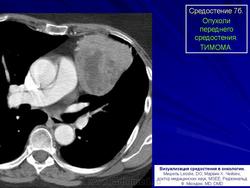

Среди опухолей переднего отдела средостения, вызывающих ограниченное расширение срединной тени, тимомы обнаруживаются чаще всего. Они могут возникнуть в любом возрасте, преимущественно у пациентов на пятом и шестом десятилетии жизни.

Рис. 1а,б. Б-ной К. 1938 года рождения. Обзорные рентгенограммы органов грудной клетки в прямой и левой боковой проекции.

Средостение на уровне передних отрезков IV ребер расширено влево дополнительным образованием, расположенным в среднем и нижнем этажах переднего отдела средостении. Наружные контуры его четкие, поверхность ровная.